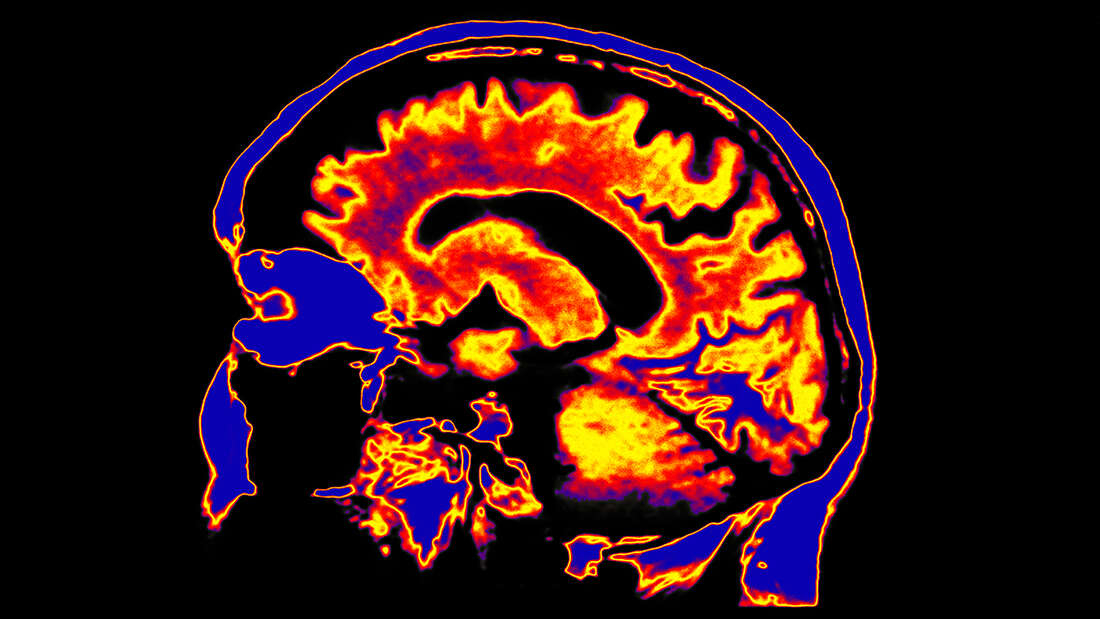

Новий огляд досліджень Covid-19 показав, що близько половини госпіталізованих пацієнтів відчувають неврологічні симптоми.

Огляд дослідників з Північно-західного університету, Школи медицини ім. Файнберга і Школи медицини Університету Колорадо, виявив, що у госпіталізованих пацієнтів були неврологічні прояви Covid-19, починаючи від більш легких симптомів, таких як головний біль, запаморочення, слабкість, м'язові болі, труднощі з концентрацією уваги, втрата нюху і смаку, завершуючи більш серйозними медичними ускладненнями, такі як судоми та інсульти.

Згідно з дослідженням, опублікованим в Annals of Neurology, захворювання може вразити мозок, спинний мозок, нерви і м'язи кількома різними способами. Захворювання вражає легені і серце, що може призвести до нестачі кисню в мозку або порушень згортання крові, які можуть привести до інсультів.

Вірус може також безпосередньо інфікувати мозок. Неврологічні симптоми також можуть бути викликані реакцією імунної системи, яка може викликати пошкодження мозку і нервів в результаті запалення.

Хоча неврологічні симптоми були виявлені приблизно у половини госпіталізованих пацієнтів, більш важкі наслідки були менш частими.

17% - запаморочення;

13% - головний біль;

7,5% -  порушення свідомості;

3% - гострі цереброваскулярні захворювання (порушення, які впливають на кровоносні судини і кровопостачання головного мозку);

0,5% - атаксія (втрата повного контролю над рухами тіла);

0,5%- судоми.

"Для широкого загалу і лікарів важливо знати про це, тому що інфекція SARS-COV-2 може спочатку мати неврологічні симптоми, перш ніж виникнуть лихоманка, кашель або респіраторні проблеми", - говорить провідний автор, доктор медичних наук Ігор Коральнік.